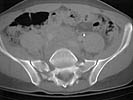

A 28 year old male jumped from the 4th floor on 11-25-2000 sustaining an L1 burst fracture that has been fixed anteriorly by the neurosurgeon with a strut between T12 and L2. A Kaneda device was placed anteriorly as well. My concern is the pelvic ring injury. There are bilateral sacral fractures through the foramen and a transverse element through the sacrum between S2 and S3. the lower part of the sacrum is displaced forward. Anteriorly there are right superior and inferior pubic rami fractures.

CT1

Axial